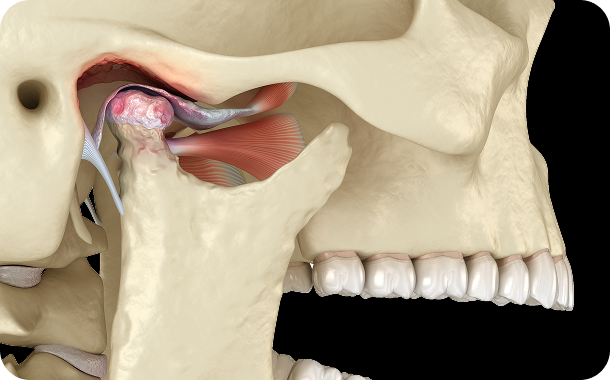

- 대한턱관절교합학회 정회원, 인정의

- 아시아 턱관절연수회 수료

- Orthognathic surgery in skeletal Class III long face with severe facial asymmetry and temporomandibular disorder(TMD) 2nd Taiwan International

Orthodontic Meeting, 2018, Poster - Changes in condylar position after 2-jaw surgery-first orthognathic surgery in a skeletal Class III patient with facial asymmetry Surgery First Summit,